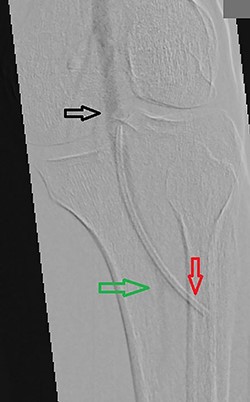

A 61-year-old male patient was diagnosed with inoperable stomach cancer. A TIVAD of the type Braun Celsite ST301® was inserted in the right subclavian vein for administration of chemotherapy. Location was confirmed by chest X-ray and the TIVAD was reported functioning with good backflow (Fig. 1). During initiation of the chemotherapy treatment, the TIVAD was reported malfunctioning. Contrast X-ray showed fibrin sheaths at the distal end of the catheter. An endovascular procedure was performed by an interventional radiologist and fibrin sheaths were mechanically removed with a snare (Fig. 2). Intraoperative X-ray with contrast showed normal contrast accumulation distal to the catheter tip and the patient received the first dose of chemotherapy. One month later the patient was hospitalized with bilateral pulmonary thromboembolism. The patient was treated with low-molecular-weight-heparin and discharged. The chemotherapy treatment continued as scheduled, with one pause due to a fracture of the right humerus after a fall. Occasionally, the TIVAD was malfunctioning and medication was administered using a peripheral venous catheter. During a planned pause in treatment, the patient sought hospital care due to worsening of his general condition. CT showed progress of malignancy and another round of chemotherapy was initiated and administrated using the TIVAD without any problems. Less than a week after, the patient reported feeling a tender swelling underneath his left foot. Ultrasound showed no DVT. The swelling and tenderness disappeared spontaneously, but the patient reported brief incidents of pain under his left foot. A CT scan was performed the next time the TIVAD did not function, showing that the distal 8 cm of the catheter was missing. The patient had no symptoms and reported no discomfort of any kind. The TIVAD was removed, confirming a fracture. A chest CT showed no foreign bodies. A full-body CT scan without contrast was performed, revealing the missing catheter part located at the level of the left knee (Figs 3 and 4). Vascular surgeons performed an endovascular procedure through the femoral vein assuming the catheter had embolized to the popliteal vein. Contrast examination revealed no catheter in the vein and another approach through the femoral artery was made, where contrast imaging shows that the catheter was, in fact, located in the popliteal artery (Fig. 5). The catheter, measuring 7.5 cm, was successfully removed with the use of a snare without any complications. The patient was discharged from hospital and referred to a diagnostic echocardiogram (Fig. 6). A bubble echocardiogram was performed to detect an atrial septal defect but was unsuccessful in doing so. For a final diagnosis, the patient was recommended a transesophageal echocardiogram, but as the diagnosis would not alter the course of treatment, the patient declined further examinations. Except for the reported episodes of pain and swelling of the left foot, the patient suffered no injury and finished his chemotherapy treatment.

Perioperative contrast imaging showing the popliteal artery (black arrow) and the posterior tibial artery (green arrow) with the tip of the catheter embolus in the anterior tibial artery (red arrow).